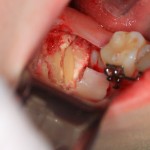

Чтобы аккуратно удалить восьмерку и не повредить соседний зуб, мы делим ее на две части. НИКАКИХ МОЛОТКОВ И ДОЛОТОВ))) Все делается, исключительно, с помощью фрез:

После чего аккуратно удаляем коронку:

А через минуту — и корни зуба. Поверьте, это очень просто, для этого не нужно прилагать каких-то усилий. Достаточно просто включить голову.